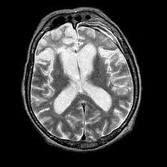

Un equipo de la Escuela de Salud Pública de Harvard, reunió información de cinco estudios grandes realizados en Estados Unidos sobre un total de más de 1 millón de adultos. Todos los participantes habían informado si fumaban o habían fumado, con qué frecuencia y durante cuántos años. Los seguimientos duraron entre siete y 28 años. El equipo pudo determinar quiénes murieron por Esclerosis Lateral Amiotrofica ELA. Según el estudio, publicado en Archives of Neurology, 832 participantes habían desarrollado ELA. Haber sido fumador o serlo elevaba un 45% el riesgo de morir por ELA. Es decir que en una década, un no fumador tenía un 0,05 por ciento de posibilidad (una en 2.000) de tener ELA, mientras que un ex fumador o fumador tenía un 0,075 por ciento (una en 1.300). El equipo halló también que comenzar a fumar tempranamente aumentaba la posibilidad de desarrollar la enfermedad. Aun así, en los fumadores no hubo relación entre la cantidad de cigarrillos consumidos por día o los años de consumo y la posibilidad de desarrollar ELA. Esta relación directa entre la "dosis" y el riesgo de enfermedad debería esperarse si el tabaquismo, en especial las sustancias tóxicas del humo, dañaran los nervios directamente, como afirman algunos expertos. Hay varios mecanismos posibles por los que fumar eleva el riesgo de desarrollar ELA, aquí, lo que vemos es quizás un cambio que altera todo el sistema de neuronas que controlan en movimiento muscular, fumar puede modificar el ADN de las células que intervienen en ese movimiento, un cambio que se acumularía en el tiempo.